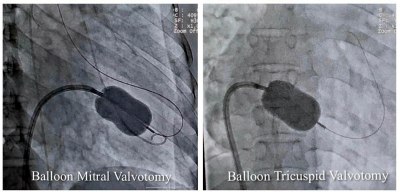

मेडिकल कॉलेज के सुपर स्पेशलिटी अस्पताल के विशेषज्ञों ने बैलून तकनीक से मिट्रल व ट्राइकसपिड वॉल्व की सिकुड़न का बिना सर्जरी के इलाज किया।

Super Specialty Hospital : रयूमेटिक हृदय रोग से पीड़ित 40 वर्षीय महिला का मेडिकल कॉलेज के सुपर स्पेशलिटी अस्पताल के विशेषज्ञों ने बैलून तकनीक से मिट्रल व ट्राइकसपिड वॉल्व की सिकुड़न का बिना सर्जरी के इलाज किया। उपचार से मरीज को धड़कन की अनियमितता, बीपी, फेफड़े, पेट व अन्य जगह पर पानी भरने में भी आराम मिला है।

कार्डियोलॉजी विभाग के हृदय रोग विशेषज्ञ और ऐसोसिएट प्रोफेसर डॉ. शिशिर सोनी ने बताया कि मरीज को अत्यधिक गम्भीर अवस्था में सुपर स्पेशलिटी अस्पताल लाया गया था। इससे पहले उसे महाकोशल के कई अस्पतालों और नागपुर के हृदय रोग विशेषज्ञों को दिखाया जा चुका था, लेकिन इलाज नहीं हो सका। डॉ. सोनी ने बताया कि मरीज के मिट्रल और ट्राइकसपिड दोनों वॉल्व में स्टेनोसिस (सिकुडऩ) थी। इस बीमारी में मरीज को अत्यधिक सांस फूलने और पैरों में सूजन की समस्या होती है। इसके अलावा अन्य समस्याएं धडकऩों की अनियमितता, कम बीपी और फेफडें, पेट और अन्य जगहों में पानी भर जाने जैसी परेशानियां भी थीं। उन्होंने बैलून तकनीक से एक ही बार में परक्यूटेनियस मिट्रल और ट्राइकसपिड बैलून वाल्यूलोप्लास्टी सफलतापूर्वक की। इलाज के बाद महिला को पूर्णत: लाभ मिला है।

डॉ. शिशिर सोनी ने बताया कि एक ही मरीज में दोनों वॉल्व की सिकुड़न का परक्यूटेनियस मिट्रल और ट्राइकसपिड बैलून पाल्यूलोप्लास्टी से सफलतम उपचार दुनिया के कुछ ही कार्डियेक सेंटर में हुआ है। मध्यप्रदेश में यह उपचार पहली बार किया गया है।